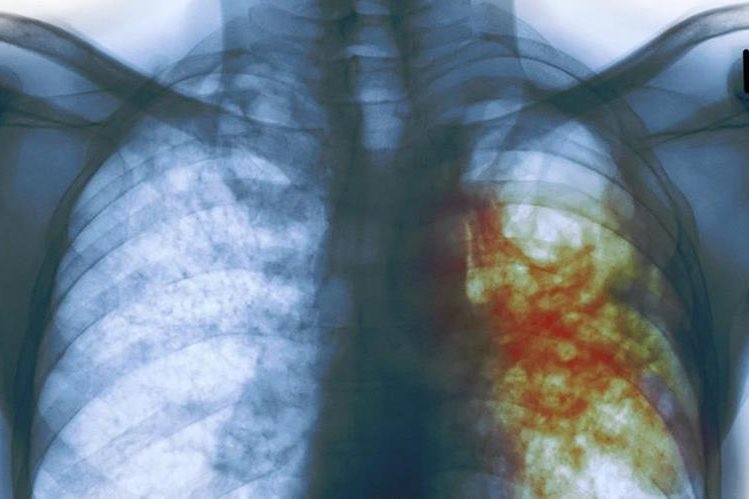

Día Mundial de la Tuberculosis: 10 datos que debe conocer sobre esta enfermedad

Qué es la tuberculosis latente que afecta a una de cada 4 personas

Según la OMS, el coronavirus pone en peligro los logros en la lucha contra la tuberculosis

The Lancet: impacto de COVID-19 puede elevar muertes por VIH, tuberculosis y malaria

Tuberculosis: la nueva cura para la cepa más mortal de la enfermedad que acaba de ser aprobada

Casos de tuberculosis en menores de edad van en aumento, este año ya se contabilizan 537

Casos de tuberculosis se incrementan en las cárceles debido al hacinamiento

Ministerio de Salud alerta sobre epidemia de tuberculosis